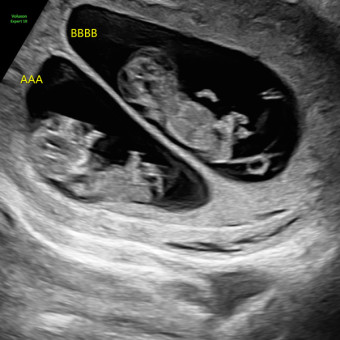

Destiny Rodriguez & Michael Simmons

Land O Lakes, FL

May 2026

Our hearts are full and our home is getting ready for two beautiful blessings. Thank you for supporting and showing love to our growing family.🌙☀️ *Gifts are preferred through registry or by mail for travel purposes.*